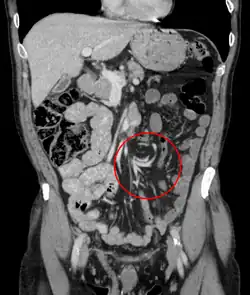

Coronal CT of the abdomen, demonstrating a volvulus as indicated by twisting of the bowel stock | |

- Coronal view of sigmoid volvulus with "whirlpool sign"